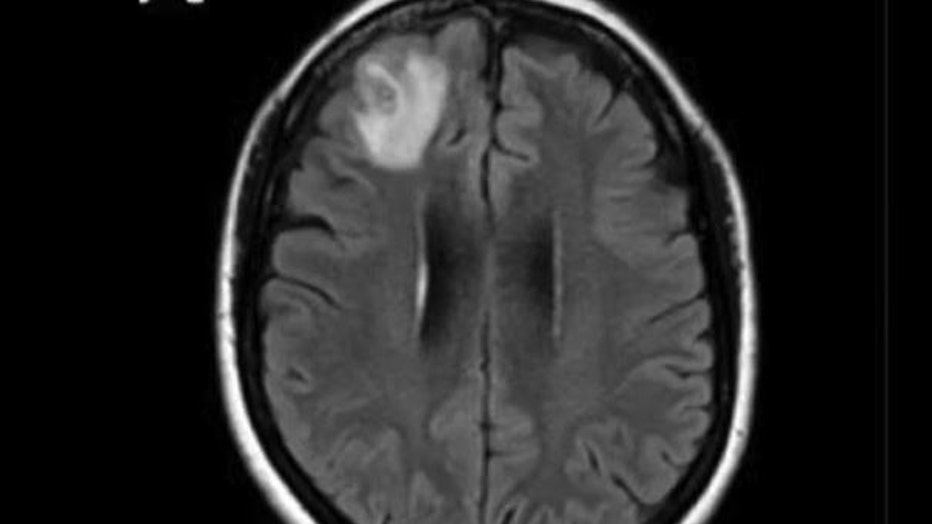

The woman had been admitted to the hospital after experiencing forgetfulness and worsening depression over three months. Scans showed changes in her brain.

Senanayake said the brain biopsy was expected to reveal a cancer or an abscess.

"This patient had been treated ... for what was a mystery illness that we thought ultimately was a immunological condition because we hadn’t been able to find a parasite before and then out of nowhere, this big lump appeared in the frontal part of her brain," Senanayake said.

Doctors removed a worm "still alive and wiggling" from a woman's brain. (Credit: Australian National University via Storyful)